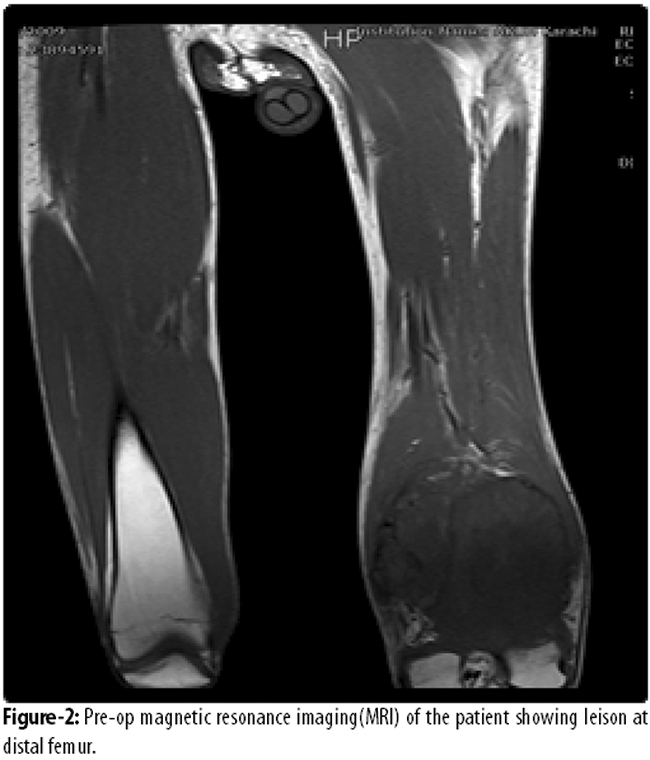

Van Nes Rotationplasty for locally advanced lower extremity tumours. A reterorespective audit was conducted at Aga Khan University Hospital (AKUH), Karachi, and comprised cases of bone and soft tissue sarcoma that underwent Van Ness Rotationplasty over seven years from January 2005 to December 2011. Demographic data, family history, past history, co-morbids, date since diagnosis, duration of symptoms, type of tumour, metastasis, pre-op and post-op functional status, recurrence and survival were collected. The preoperative work-up included routine radiographs, bone and soft-tissue scintigraphy, magnetic resonance imaging (MRI) of the lesion and computed tomography (CT) scan of the chest.

The operative technique was that of wide margin excision. The extent of bony resection was planned on MRI of the diseased region. The minimum margin of resection was 3cm from the maximum extent of the disease. The resection extent was planned so at skeletal maturity the heel of the rotated foot would come to the knee of the normal side. In a skeletally mature patient, this would be achieved at the time of surgery. In a skeletally immature patient, the operated limb would be kept longer. The skin incision was rhomboid with the apex at the level of the proximal bone cut and the distal arms meeting at the level of distal cut. The two oblong arms of the skin incision met posteriorly both proximally and distally. The posterior cuts were then joined by a single vertical posterior incision.

Patients were kept in house for 5 to 6 days postoperatively. Drains were not used. On day 12 stitches were removed. When the wound got healed and bone ends were progressing well, the patients were fitted with external prosthesis and encouraged to walk usually at 6 weeks. The patients were followed up regularly in the outpatient department (OPD) for a period ranging from 6 months to 34 months (Figures 1-5).

Of the 351 cases of bone and soft tissue sarcoma, 9(2.6%) underwent Van Ness Rotationplasty and were included in the study; 5(55.6%) females and 4(44.4%) males. Age ranged from 7 to 39 years with a mean of 15±2SD years. The mean duration of symptoms was 7±3 SD months (range: 8-41 months). Eight (88.9%) were osteogenic sarcomas, and 1(11.1%) had squamous cell carcinoma of knee. Besides, 8(88.9%) involved distal femur. Overall, 7(77.8%) had localised Enneking stage IIB disease.